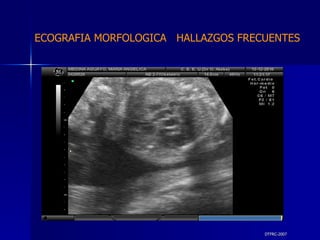

DTFRC-2007 ECOGRAFIA MORFOLOGICA  HALLAZGOS FRECUENTES   MATERIAL Y METODO ES UN ESTUDIO DESCRIPTIVO, RETROSPECTIVO  DE ESTUDIO ECOGRA FICOS REALIZADOS ENTRE MARZO 07 A MARZO 08 EQUIPO DE ALTA RESOLUCION   VOLUSON 730 PRO  MEDISON SA 8000 live MEDISON SA 8000SE CRITERIO DE INCLUSION:   POBLACION GENERAL    GESTACIONES  20 a 24 SEMANAS   UNIVERSO  N 211

DTFRC-2007 ECOGRAFIA MORFOLOGICA  HALLAZGOS FRECUENTES   Sistema Nervioso Central  8  Cardiovascular  0 Genitourinario  6 Musculos Esqueleticos  2 Gastrointestinales  2  Otros  12  Total  30   NUMEROS DE ANOMALIAS POR SISTEMA n N  211

DTFRC-2007 ECOGRAFIA MORFOLOGICA  HALLAZGOS FRECUENTES   SISTEMA NERVIOSO CENTRAL TOTAL  8  26 % 1 HIDROCEFALIA 2 VENTRICULO MEGALIA 4 QUISTE DE PLEXO COROIDEO 1 ANENCEFALIA